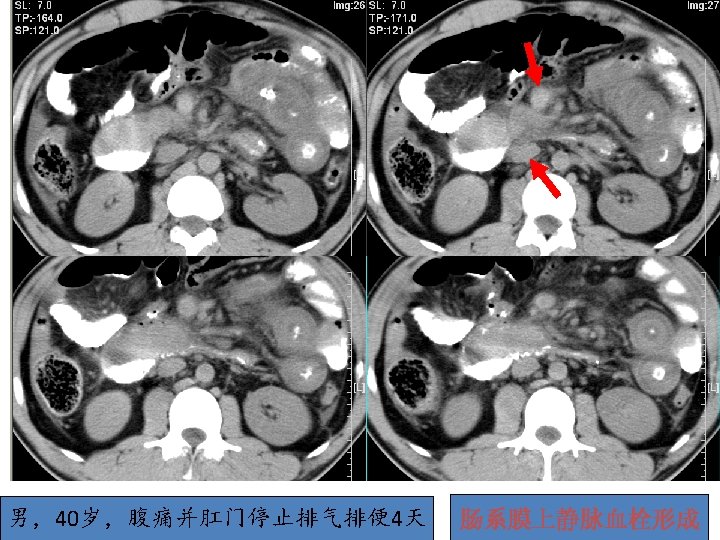

Target sign A 27 -year-old male presented with abdominal pain of 10 hours duration 肠系膜上静脉血栓形成